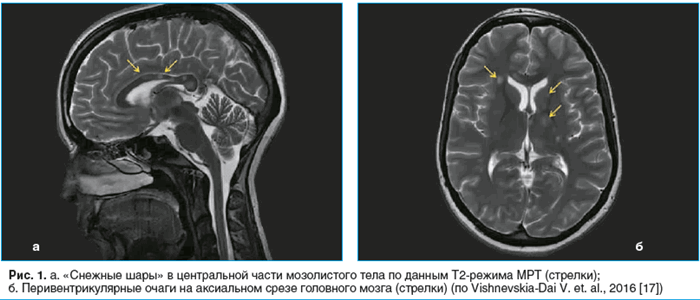

![Рис. 1. a. «Снежные шары» в центральной части мозолистого тела по данным Т2-режима МРТ (стрелки); б. Перивентрикулярные очаги на аксиальном срезе головного мозга (стрелки) (по Vishnevskia-Dai V. et. al., 2016 [17])]()

В дифференциальной диагностике синдрома Сусака важное значение придается нейрорадиологическим исследованиям [16]. Патогномоничным считается выявление с помощью магнитно-резонансной томографии (МРТ) головного мозга множественных гиперинтенсивных сигналов в центральной части мозолистого тела. При введении парамагнетика происходит обогащение патологических очагов, выявляемых на Т2-взвешенных изображениях. Помимо типичных изменений в виде маленьких или больших «снежных шаров» или линейных дефектов в центральной части мозолистого тела (рис. 1а, б) [17] у 70% больных имеется поражение серого вещества, а у 33% — оболочек мозга [18]. По данным МРТ (диффузионно-взвешенный режим) в этой области выявляются очаги высокой интенсивности. Режим 3D-FLAIR также выявляет вовлечение в патологический процесс мягкой мозговой оболочки [19]. Необходимо помнить, что, в отличие от рассеянного склероза, для синдрома Сусака образование патологических очагов в спинном мозге нехарактерно. МРТ головного мозга позволяет проводить раннюю диагностику синдрома Сусака и, соответственно, своевременную патогенетическую терапию [5, 11, 20].

![Рис. 1. a. «Снежные шары» в центральной части мозолистого тела по данным Т2-режима МРТ (стрелки); б. Перивентрикулярные очаги на аксиальном срезе головного мозга (стрелки) (по Vishnevskia-Dai V. et. al., 2016 [17])](/pimg1/sindrom-susaka-mrt-73871.png)